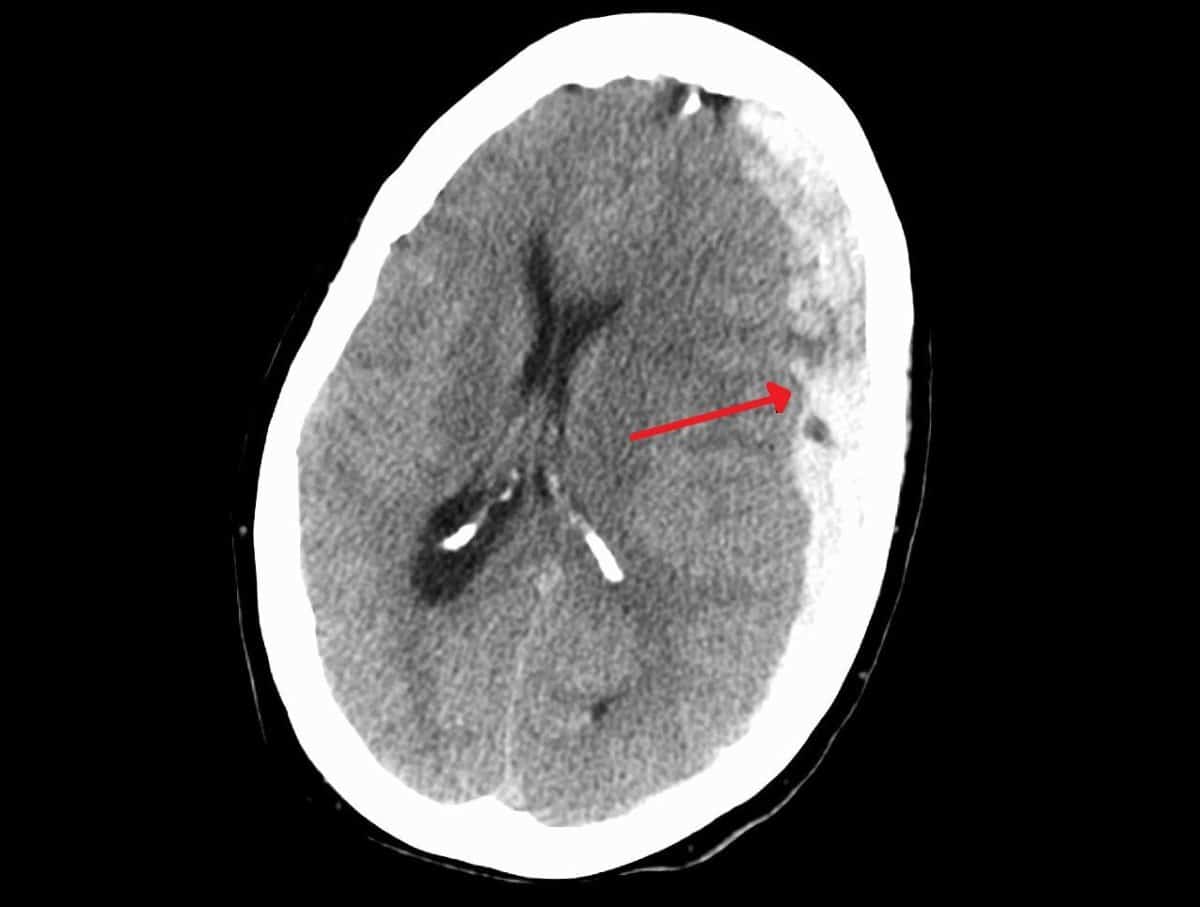

Ежегодно в России регистрируется около 600 тысяч случаев черепно-мозговых травм, причем до 40% всех внутричерепных кровоизлияний составляют субдуральные гематомы. Это опасное состояние, возникающее при разрыве сосудов между мозгом и черепом, приводит к сдавлению мозга и требует экстренного выбора лечения — консервативного или хирургического. Особую тревогу вызывает высокая летальность при обширных субдуральных гематомах, а также риск повторных кровоизлияний, с которыми сталкивается каждый третий пациент, принимающий препараты для разжижения крови. Ученые ПГМУ им. академика Е.А. Вагнера и ПНИПУ создали и запатентовали компьютерную программу, прогнозирующую перспективы лечения. В основу алгоритма легли клинические исследования, позволившие выделить ключевые прогностические факторы: возраст пациента и расположение гематомы. Система анализирует и другие параметры — объем кровоизлияния, время до госпитализации и прием антикоагулянтов. Разработка поможет врачам не только выбирать оптимальную тактику лечения, но и объективно оценивать шансы пациента на восстановление.

Травматическая субдуральная гематома — коварное и опасное последствие черепно-мозговой травмы, при котором кровь из поврежденных сосудов начинает скапливаться в узком пространстве под черепом, сдавливая мозг. Особую группу риска составляют пожилые пациенты: с возрастом мозг становится более уязвимым, а широкий прием антикоагулянтов (препаратов для разжижения крови), необходимых для профилактики инфарктов и инсультов, многократно повышает риск тяжелых последствий даже после незначительного падения или ушиба. Согласно данным клинических исследований смертность от таких травм достигает 10-14%, а каждый седьмой выживший пациент становится инвалидом. Ситуацию усугубляет сложность диагностики: хроническая гематома может неделями «маскироваться» под другие возрастные заболевания, такие как деменция или инсульт.

Высокая летальность и непредсказуемость результатов лечения побудили пермских ученых из ПГМУ им. академка Е.А. Вагнера и ПНИПУ сосредоточиться на выявлении объективных критериев, позволяющих прогнозировать результат лечения. Эксперты проанализировали случаи пациентов со схожими гематомами, поступивших в клинику в первые 6 часов после травмы. Всех пациентов разделили на три группы по расположению гематомы: лобно-височная, теменно-височная и лобно-теменно-затылочная области. Поскольку помощь всем оказали в одинаково сжатые сроки, врачи смогли объективно оценить, как локализация кровоизлияния влияет на результаты лечения. Исследователи выявили закономерность: среди всех пациентов, достигших хороших результатов лечения (60% от общего числа), на долю пациентов с гематомой в лобно-височной области пришлось 35% всех успешных исходов — это самый высокий показатель. Если кровоизлияние происходило в лобно-теменно-затылочной области, ситуация значительно ухудшалась: такие гематомы имели статистически больший объем, а пациенты поступали в более тяжелом состоянии.